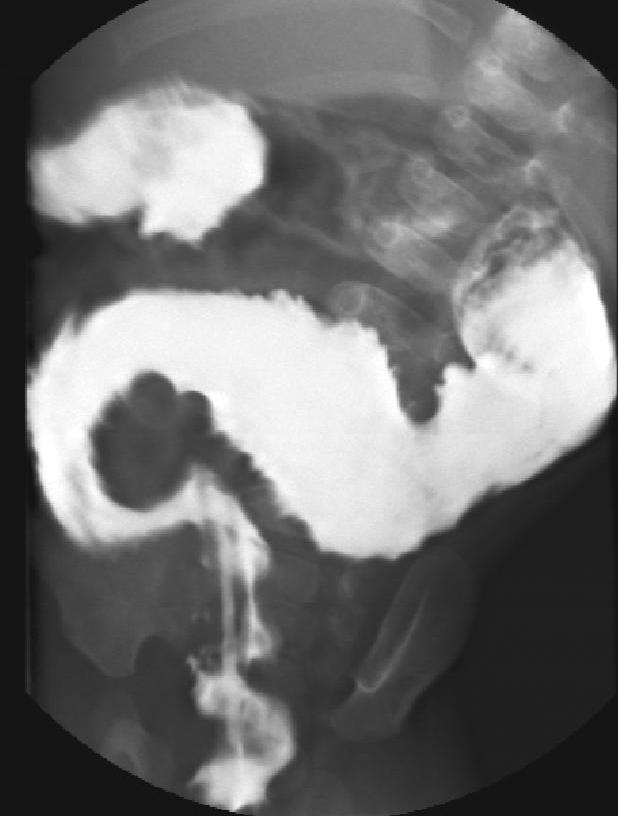

Malrotation-volvulus. During the normal development of the intestinal tract, the intestinal loops make three 90 degree clock-wise rotations around the mesenteric superior artery (MSA.) If this rotation only partially occurs during the embryonic development the intestines remain in a non-rotational or malrotational position, the mesenteric root will be shorter and the cecum will be weakly attached. This anatomic positioning can be symptom free throughout a lifetime, but it predisposes for volvulus. Volvulus can occur at any age, but it is most frequent in the first months of life, when it abruptly occurs with acute bilious vomiting. In this state the intestines around the mesenteric root twist, end up in a complete obstruction that can lead to a rapid death of the intestines. Ultrasonography can depict the mesenteric superior vein (MSV) coiled up around the MSA, so called “whirlpool”-sign.

During X-ray examination the contrast material does not progress to the jejunal loops or it shows a “corkscrew” sign on the right side of the vertebrae as it piles up in the twisted intestinal loops.

Image

15. Contrast material empties the stomach slowly, small intestines are found on the right side of the abdomen. Malrotation-volvulus.